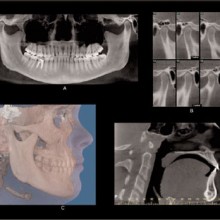

Each voxel is small (0.1-0.4 mm for each of the cube faces) and therefore the image has a relatively high resolution. The field of view can be adjusted to include a portion of or the entire maxillofacial region. The CBCT software allows for reformatting and viewing the image data from my point of view in straight or curved planes and in three-dimensions (Figure 1). Using these software tools the anatomy can be peeled away layer by layer to locate the desired anatomy. The CBCT ranks extremely high when considering the balance between high diagnostic yield, low cost, and low risk (Mah et al).

A tremendous amount of anatomic information is contained within the voxel volumes, and this information can be retrieved, analyzed, and viewed at a computer workstation using visualization and/or analytic software. The computer monitor is a two-dimensional, eight-bit display used to visualize three-dimensional, twelve-bit image data. The twelve-bit data can be viewed on an eight-bit display by using the technique of windowing, which allows for visualization of the entire 4096 shades of grey; eight bits at a time. Often, the anatomic volumes are acquired as voxel layers, and stacked as a series of parallel cross sections of the anatomy. These stacks can be displayed and viewed as a series of two-dimensional cross sections by sequentially paging through them in orthogonal planes (sagittal, axial, coronal). This is called multiplaner reformatting (MPR). MPR is the two-dimensional display of three-dimensional data in multiple projection planes (Figures 2a, 2b). Spatial relationships between three simultaneous displayed planes are communicated by projecting one plane onto the corresponding orthogonal planes as lines. Since the anatomic structures of interest occupy multiple layers within a stack, the clinician needs to perform a mental reconstruction of the anatomy. Coronal, sagittal, and axial views can be linked with synthesized views, such as oblique and/or curved slices or slabs. Slices or slab thickness can be manipulated directly and in real-time. The volume or slab of image data can be viewed with different modes of display, including MIP, SSR, and VR.

MAXIMUM INTENSITY PROJECTION (MIP) can be used to highlight features. The anatomic features associated with the brightest pixel or voxel intensity are projected on the display screen. This method creates a high-contrast image, but the brighter pixels/voxels may mask or superimpose over less-bright pixels, thus potentially hiding important anatomic features. MIP projections of a CBCT volume or slab (right or left sides) may be a useful method to produce constructed panoramic and cephalometric images for orthodontic purposes (Figure 3). Shaded surface Rendering (SSR) is useful for high-contrast imaging such as bone. SSR techniques allow the operator to set a pixel or voxel intensity threshold that excludes structures lower than the selected threshold, and renders all structures greater than the selected threshold (Figure 3). SSR creates a three-dimensional model that can be rotated as an object to be viewed from any angle. When the tissue contrast is not high, then the selected threshold may not perfectly render the desired anatomy. Volume rendering (VR) also creates a three-dimensional model using no